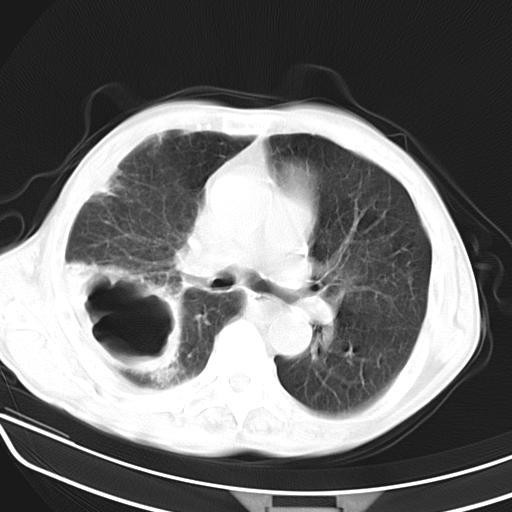

男,70,发烧咳嗽咳痰10余天,查痰结核菌阴性。否认以前有肺病史。治疗10天后症状减轻。 img]/upload/forum/2009/12/302117469692.jpg[/img]

影像所见:右上肺见一巨大厚壁空洞,内壁欠光整,右上肺广泛斑片状、大片状模糊阴影。

影像所见:右上肺见一巨大厚壁空洞,并见分隔,内壁欠光整,右上肺广泛斑片状、大片状磨玻璃阴影。